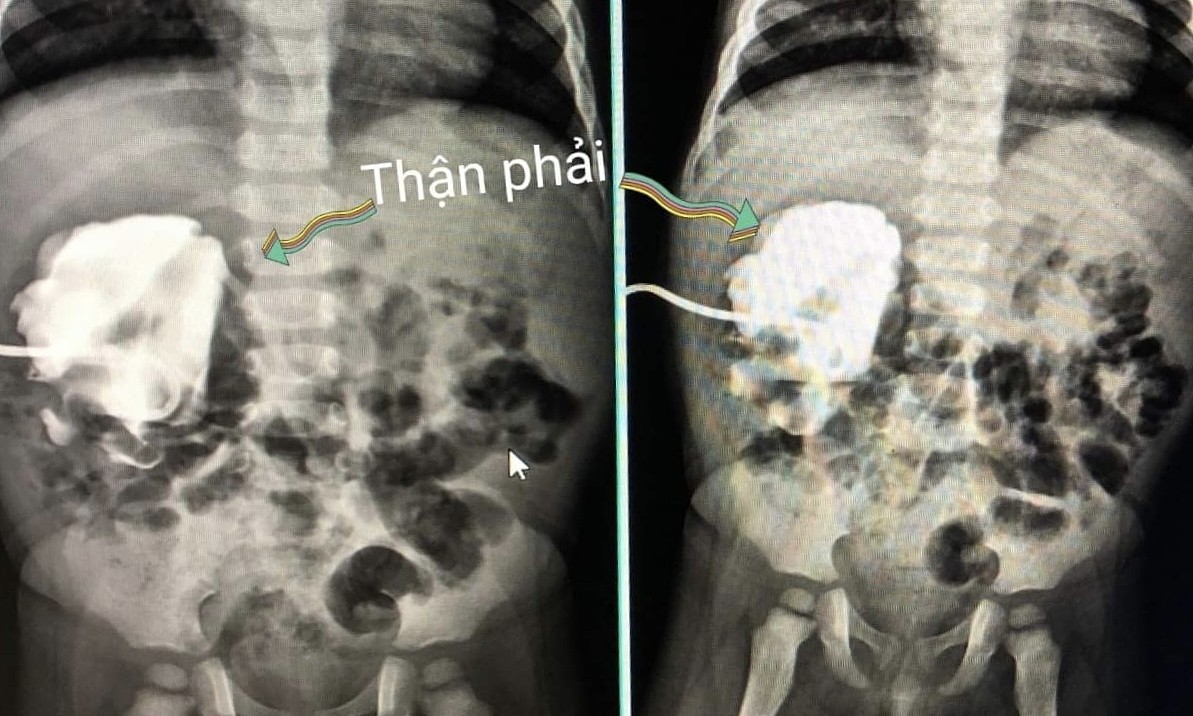

Đầu tháng 11, bác sĩ tình nguyện về địa phương khám sức khỏe, thấy bụng bé chướng căng bất thường, khuyên xuống bệnh viện Sản nhi tỉnh kiểm tra. Kết quả siêu âm cho thấy trẻ chỉ còn một bên thận, có biểu hiện suy thận, ứ nước, nghi u thận. Do tiên lượng bệnh nhân nặng, các bác sĩ đã dẫn lưu thận cấp cứu rồi chuyển trẻ xuống Bệnh viện E (Hà Nội) phẫu thuật.

Tiếp nhận bệnh nhân, TS.BS Nguyễn Đình Liên, Trưởng Khoa Phẫu thuật thận Tiết niệu và Nam học, cho biết trẻ mắc bệnh lý thận bẩm sinh, khó và hiếm gặp. Bệnh nhân bị đa dị tật hệ tiết niệu, một quả thận bị teo nhỏ bẩm sinh, không còn chức năng.

"Nếu không phát hiện và phẫu thuật, quả thận còn lại có nguy cơ hỏng hoàn, phải chạy thận suốt đời, thậm chí tử vong", bác sĩ nói và thêm rằng trường hợp này phải nội soi gây mê tạo hình niệu quản mới giữ được thận. Khó khăn khác, trẻ nhỏ, sức khỏe yếu, 4 tuổi nặng 10 kg, cơ thể suy kiệt.